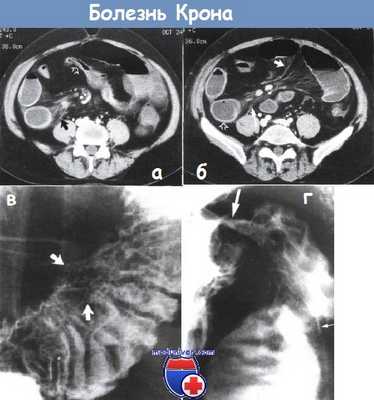

а - болезнь Крона. Отрезок подвздошной кишки сужен, стенка кишки немного утолщена (густая стрелка). Воспалительные тяжи (черная стрелка) в брыжейке тонкого кишечника. Компьютерная томография, аксиальное изображение на уровне пупка.

б - некоторое утолщение стенки двух кишечных петель (пустая стрелка). Воспалительные тяжи в брыжейке тонкого кишечника (длинная стрелка). Воспалительные тяжи в брыжейке напоминают гребень (короткая стрелка) и отражают сосудистые изменения и перилимфатическое воспаление. Компьютерная томография на уровне подвздошных гребней того же пациента, что и на рисунке (а).

в - увеличение кишечных ворсинок при болезни Крона. В дистальной части подвздошной кишки заметно пять узелков (указаны стрелкой), кишечные ворсинки увеличены из-за отека и воспалительной инфильтрации. Высокая бариевая клизма.

г - болезнь Крона терминального отрезка подвздошной кишки. Заметна длинная язва на брыжеечном крае кишки в виде тонкого углубления, заполненного барием (тонкие стрелки), окруженная отечной возвышенной рентгенопрозрачной слизистой оболочкой. Слизистая оболочка дистальной части терминального отрезка подвздошной кишки узловатая.

Илеоцекальный клапан сужен (толстая стрелка). Рентгеноконтрастное исследование с барием.